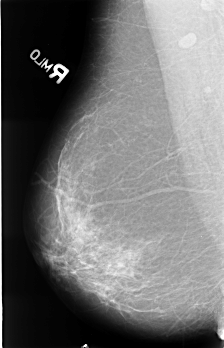

B_3476_1.RIGHT_MLO

LEFT_MLO LINES 4456 PIXELS_PER_LINE 2904 BITS_PER_PIXEL 12 RESOLUTION 50 OVERLAY

FILE: B_3476_1.LEFT_MLO.OVERLAY

TOTAL_ABNORMALITIES 1

ABNORMALITY 1

LESION_TYPE CALCIFICATION TYPE PLEOMORPHIC DISTRIBUTION CLUSTERED

ASSESSMENT 4

SUBTLETY 3

PATHOLOGY MALIGNANT

TOTAL_OUTLINES 1

BOUNDARY